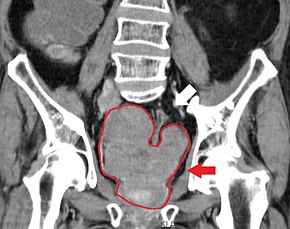

Prostate cancer that has metastasized to the lymph nodes

Prostate cancer that has metastasized to the bone

Prostate cancer is considered a malignant tumor because it can invade other areas of the body. This invasion is called metastasis. Prostate cancer most commonly metastasizes to the bones and lymph nodes, and may invade the rectum, bladder, and lower ureters after local progression. The route of metastasis to bone is thought to be venous, as the prostatic venous plexus draining the prostate connects with the vertebral veins.[63]

If already having grown large, a prostate cancer may first be detected on CT scan.